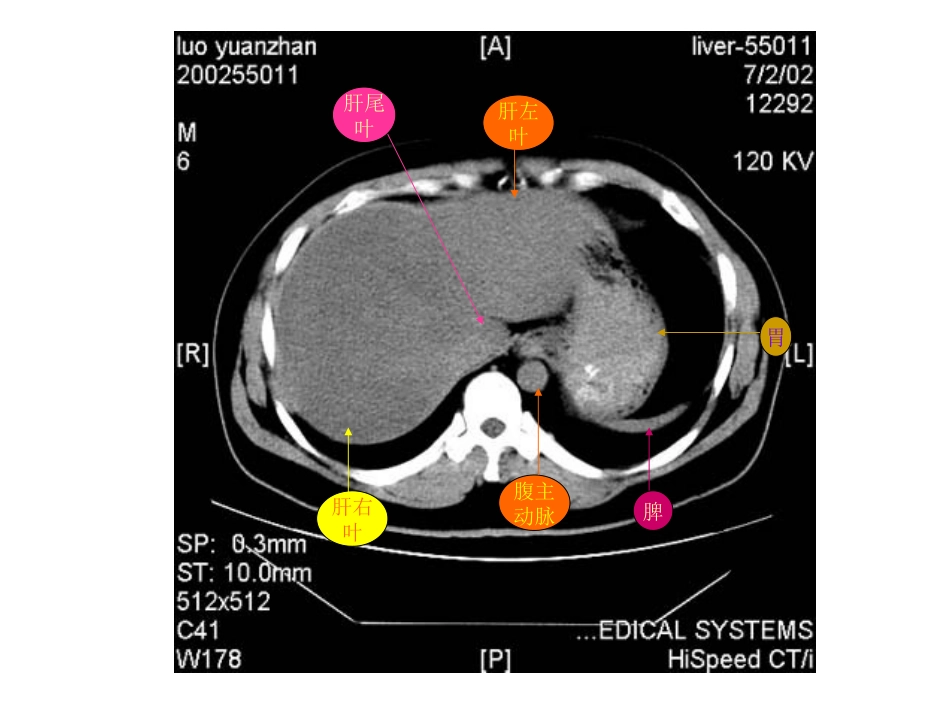

肝右叶横膈肺胸椎脊髓腹主动脉食管肋骨肋骨肝右叶腹主动脉食管肺肝左叶肝右叶腹主动脉胃脾肝尾叶肝右叶尾叶膈脚脾门静脉肝左叶胃肝右叶膈脚腹主动脉脾胆囊胃肝右叶下腔静脉胰腺脾胃腹主动脉肝右叶心脏腹主动脉下腔静脉脊髓食管肺肝左叶肝右叶腹主动脉下腔静脉胃脾脊髓肝左叶及肝左动脉肝右叶及肝右动脉腹主动脉下腔静脉胃脾肝尾叶肝右叶下腔静脉腹主动脉胃脾膈脚肝静脉下腔静脉腹主动脉食道肝右叶下腔静脉肝右叶肝静脉肝左叶腹主动脉胃脾肝尾叶肝右叶下腔静脉腹主动脉门静脉主干肝左叶胃脾肝右叶下腔静脉门静脉腹主动脉膈脚脾胃肝血管瘤CT平扫呈低密度灶,密度均匀,边缘较清。肝血管瘤静脉注入造影剂后CT扫描,动脉期示:病灶由边缘向中心结节状强化,逐渐填满,其密度与同层腹主动脉相似。腹主动脉肾肝血管瘤静脉期示病灶进一步强化填充,呈密度较均的高密度灶,显示更清楚。肝血管瘤2分钟后,平衡期CT扫描示病灶仍呈较高密度,显示清楚,表现为“早出晚归”征肝血管瘤CT平扫示肝脏左右叶普遍增大。静脉注入造影剂后CT扫描,静脉期示肝实质呈不均匀强化。门静脉肝硬化:CT平扫示肝脏左右叶体积缩小,边缘欠平整,肝裂增宽肝裂增宽肝硬化并门静脉高压,静脉注入造影剂后静脉期CT扫描示:脾门静脉曲张。脾门静脉曲张脾肝右叶肝左叶肝癌CT平扫示:肝脏体积明显增大,边缘不平整,肝实质密度不均,内见结节状、团块状低密度癌灶,边缘模糊,密度不均。肝右叶巨大癌灶肝内结节状癌灶静脉注入造影剂后CT扫描,动脉期示:肝内癌灶不均匀增强,密度增高,其内见肿瘤坏死部分不强化,呈更低密度。癌灶增强,密度增高瘤内坏死部分呈更低密度静脉早显肿瘤血管肿瘤假包膜静脉注入造影剂后CT扫描,静脉期示下腔静脉内癌栓呈低密度充盈缺损表现。肝右叶癌灶腹主动脉静脉注入造影剂后CT扫描,静脉期示:由于造影剂洗脱,肿瘤呈较低密度。本例见癌肿侵犯门静脉,门脉左支受压变形,门脉右支未见显影。门静脉左支受压变形肝内癌灶静脉注入造影剂后CT扫描,平衡期示:肝内癌灶随造影剂进一步洗脱呈低密度表现。本例门静脉左支内还可见稍低密度癌栓。门静脉左支及其内癌栓肝内癌灶胆囊体积缩小,胆囊壁稍厚。肾胰肝肾静脉腹主动脉慢性胆囊炎CT平扫示:胆囊体积缩小,胆囊后壁见一类椭圆形高密度结石胆囊结石腹水肝胰肠管脾腹水肾正常胰腺CT平扫胰腺体、尾部胆囊肝右叶脾肠管下腔静脉膈脚腹主动脉正常胰腺CT平扫肝右叶胰头肠管肾腹主动脉下腔静脉静脉注入造影剂后,正常胰腺CT对比增强扫描胆囊肝右叶下腔静脉胰体胰尾脾肾肠管脾静脉静脉注入造影剂后,正常胰腺CT对比增强扫描胰头下腔静脉肝右叶腹主动脉肾肠管脾静脉脾急性单纯性胰腺炎CT平扫胰腺肝脾左肾下腔静脉腹主动脉胃急性单纯性胰腺炎CT平扫胰腺脾右肾肝下腔静脉腹主动脉胆囊胃急性单纯性胰腺炎CT平扫胰头胃肝胆囊脾左肾下腔静脉腹主动脉肠管急性单纯性胰腺炎CT对比增强扫描胰腺胃胆囊肝下腔静脉腹主动脉脾静脉左肾脾急性单纯性胰腺炎CT对比增强扫描腹主动脉脾静脉下腔静脉胰头肝胆囊胃左肾脾肠管急性渗出性胰腺炎CT平扫胰腺胃肝脾右肾下腔静脉腹主动脉急性渗出性胰腺炎CT平扫胰腺胃肝脾腹主动脉下腔静脉右肾肾前筋膜增厚胆囊急性渗出性胰腺炎CT平扫胰腺胃胆囊肝右肾下腔静脉腹主动脉肾前筋膜增厚左肾脾慢性胰腺炎CT增强扫描示:胰管扩张胰腺扩张胰管胃胆囊增大肝右肾右肾静脉腹主动脉左肾左肾静脉脾胰腺体积缩小胰腺胃脾左肾肝右叶肝左叶下腔静脉腹主动脉